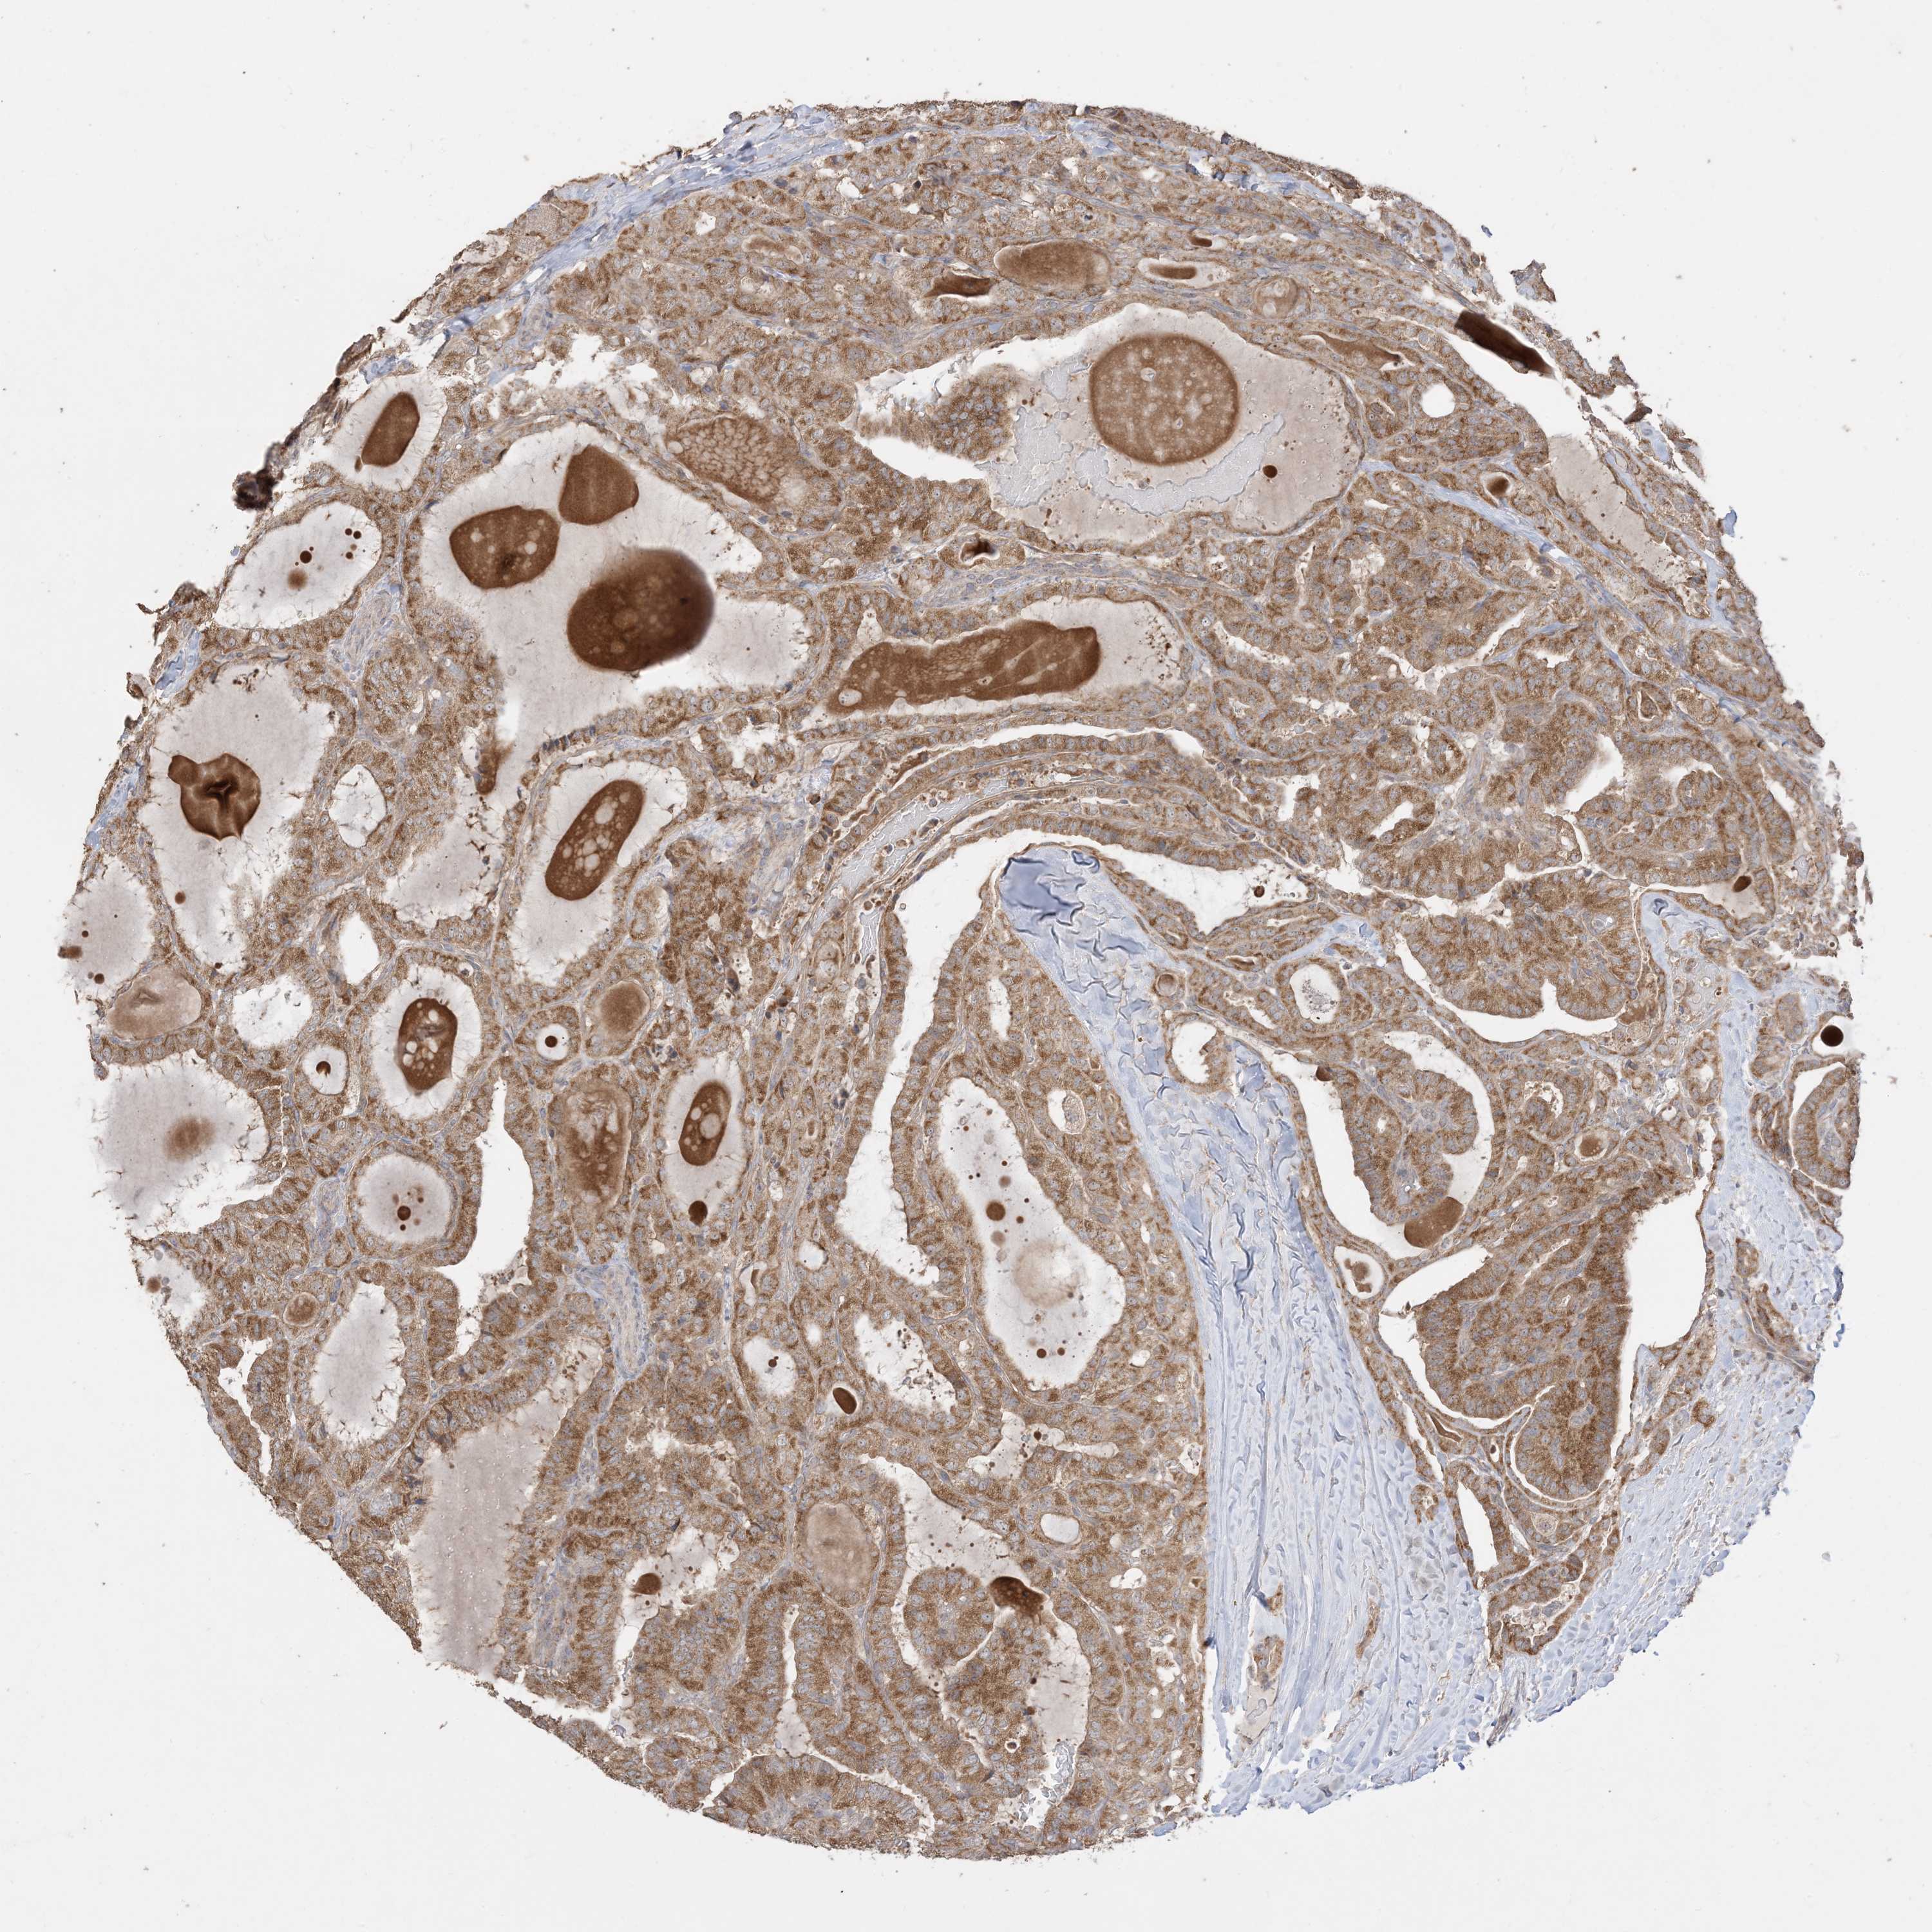

THYROID CANCER - Protein expressioni

A mouse-over function shows sample information and annotation data. Click on an image to view it in a full screen mode. Samples can be filtered based on level of antibody staining by selecting one or several of the following categories: high, medium, low and not detected. The assay and annotation is described here.

Note that samples used for immunohistochemistry by the Human Protein Atlas do not correspond to samples in the TCGA dataset.

Antibody stainingi

Antibody staining in the annotated cell types in the current human tissue is reported as not detected, low, medium, or high, based on conventional immunohistochemistry profiling in selected tissues. This score is based on the combination of the staining intensity and fraction of stained cells.

Each image is clickable and will lead to virtual microscopy that enables deeper exploration of all samples and also displays staining intensity scores, fraction scores and subcellular localization as well as patient and tissue information for each sample.

Antibody CAB037142

Staining

High

Medium

Low

Not detected

Intensity

Strong

Moderate

Weak

Negative

Quantity

>75%

75%-25%

<25%

None

Location

Nuclear

Cytoplasmic/membranous

Cytoplasmic/membranous,nuclear

Papillary adenocarcinoma, NOS

Follicular adenoma carcinoma, NOS